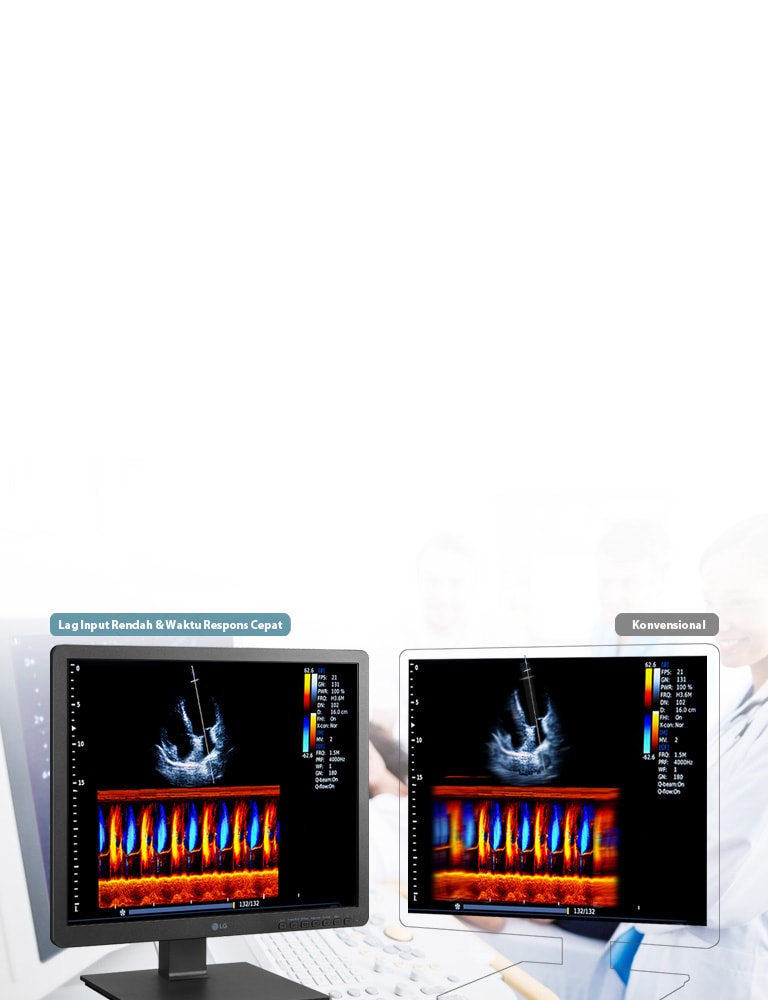

Picture) - Dynamic Sync Mode (Thru Mode)